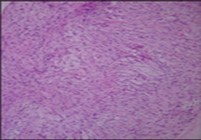

Macroscopically,the neoplasm is gradually progressive, painless, firm, tan coloured, well circumscribed, grossly infiltrative, soft tissue mass of magnitude varying from one centimetre to 18 centimetres, commonly of 6 centimetres diameter. Cut surface is fibrotic with focal myxoid areas4. On fine needle aspiration cytology, the cellular neoplasm is configured by spindle-shaped cells. Tumour cells contain scant, wispy cytoplasm, uniform, elongated nuclei and miniature, inconspicuous nucleoli. The background is prominently myxoid. Significant nuclear pleomorphism or mitotic activity is absent. However, cogent diagnosis on cytology may be challenging 4.5. On low power, the well demarcated neoplasm is composed of alternating foci of myxoid and fibrous tissue. Giant rosettes are intermingled with zones of whorled cellular aggregates recapitulating preliminary rosettes.

Bland tumour cells depict monotonous, hyperchromatic nuclei. Tumour areas can exhibit prominent curvilinear, arching or plexiform vasculature. Mitotic activity is exceptional 4, 5.

Typically, low grade fibromyxoid sarcoma is comprised of a whorled cellular pattern with intermingled fibrous and myxoid areas. Also, minimally cellular areas of collagenous tissue are denominated, composed of uniform spindle-shaped cells4, 5. Unique morphologic pattern of hyalinising spindle cell tumour configuring giant rosettes can appear in certain low grade fibromyxoid sarcomas4, 5.

The minimally to moderately cellular neoplasm is composed of bland, fusiform or spindle-shaped cells with scarce cytoplasm and angulated nuclei. Also, whorled cellular aggregates are exhibited. Focal to diffuse cellular whorls are intermingled within a dense, collagen-rich stroma. Abrupt, focal transition to myxoid areas can be discerned. Roughly 45% neoplasms depict foci of epithelioid cells. Nearly 40% tumours display enlarged, inadequately configured collagen rosettes2, 4.

The neoplasm frequently infiltrates abutting skeletal muscle. Occasionally, tumefaction denominates hyper-cellular foci, tumour necrosis, cellular or nuclear atypia and mitotic figures, features which are characteristic of intermediate to high grade sarcoma. Localized tumour reoccurrence may be hyper-cellular with enhanced mitotic activity 4, 5. On ultrastructural examination, fibroblastic differentiation is exemplified 5. Figure 1, Figure 2, Figure 3, Figure 4, Figure 5, Figure 6, Figure 7, Figure 8.

Figure 7.Low grade fibromyxoid sarcoma depicting alternating fibrous and myxoid regions with bland, spindle-shaped tumour cells and absent mitosis (15).

Figure 8.Low grade fibromyxoid sarcoma delineating alternating fibrous and myxoid areas of minimal cellularity and mitosis (9).